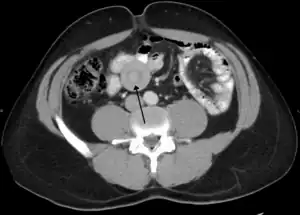

An intussuception as seen on CT

An intussusception is often suspected based on history and physical exam, including observation of Dance's sign. A digital rectal examination is particularly helpful in children, as part of the intussusceptum may be felt by the finger. A definite diagnosis often requires confirmation by diagnostic imaging modalities. Ultrasound is the imaging modality of choice for diagnosis and exclusion of intussusception, due to its high accuracy and lack of radiation. The appearance of target sign (also called "doughnut sign" on a sonograph, usually around 3 cm in diameter, confirms the diagnosis. The image seen on transverse sonography or computed tomography is that of a doughnut shape, created by the hyperechoic central core of bowel and mesentery surrounded by the hypoechoic outer edematous bowel.[8] In longitudinal imaging, intussusception resembles a sandwich.[8] It is also called "pseudokidney" sign because hyperechoic tubular centre is covered by a hypoechoic rim producing a kidney-like appearance.[9]